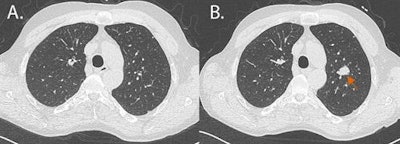

Germany's healthcare system has early detection programs for breast, cervical, colon, and other cancers. In recent years, bronchial carcinoma has been added to the list of cancers for which screening can be effective, using a low-dose CT scan of the lungs. Some features of latest-generation CT scanners, such as iterative reconstruction, require only about a fifth of the radiation dose normally required for diagnostic CT scans of the lungs, thus reducing the risks associated with radiation exposure.

CT screening should look for the typical round lesions of lung cancer and also early-stage COPD or atherosclerosis, both of which are caused by smoking, according to Kauczor. "And finally, it's vital that CT screening for lung cancer should include stopping smoking and prevention programs if it's to be comprehensive and attractive to smokers," he noted. This is also the message of a joint position paper by European radiology and pulmonology bodies.